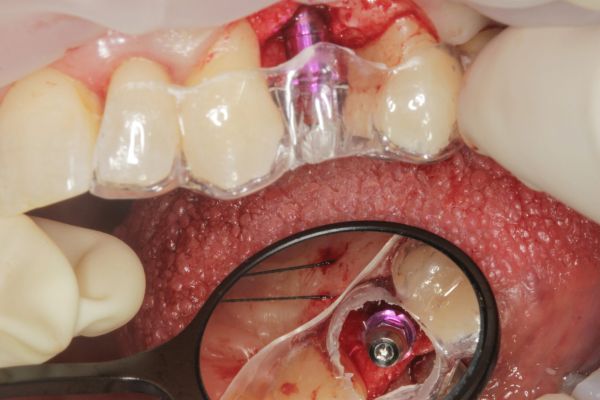

Manejo quirúrgico y restaurador de un implante en área estética y evaluación volumétrica tras un injerto de tejido conectivo desepitelizado. Descripción de un caso clínico